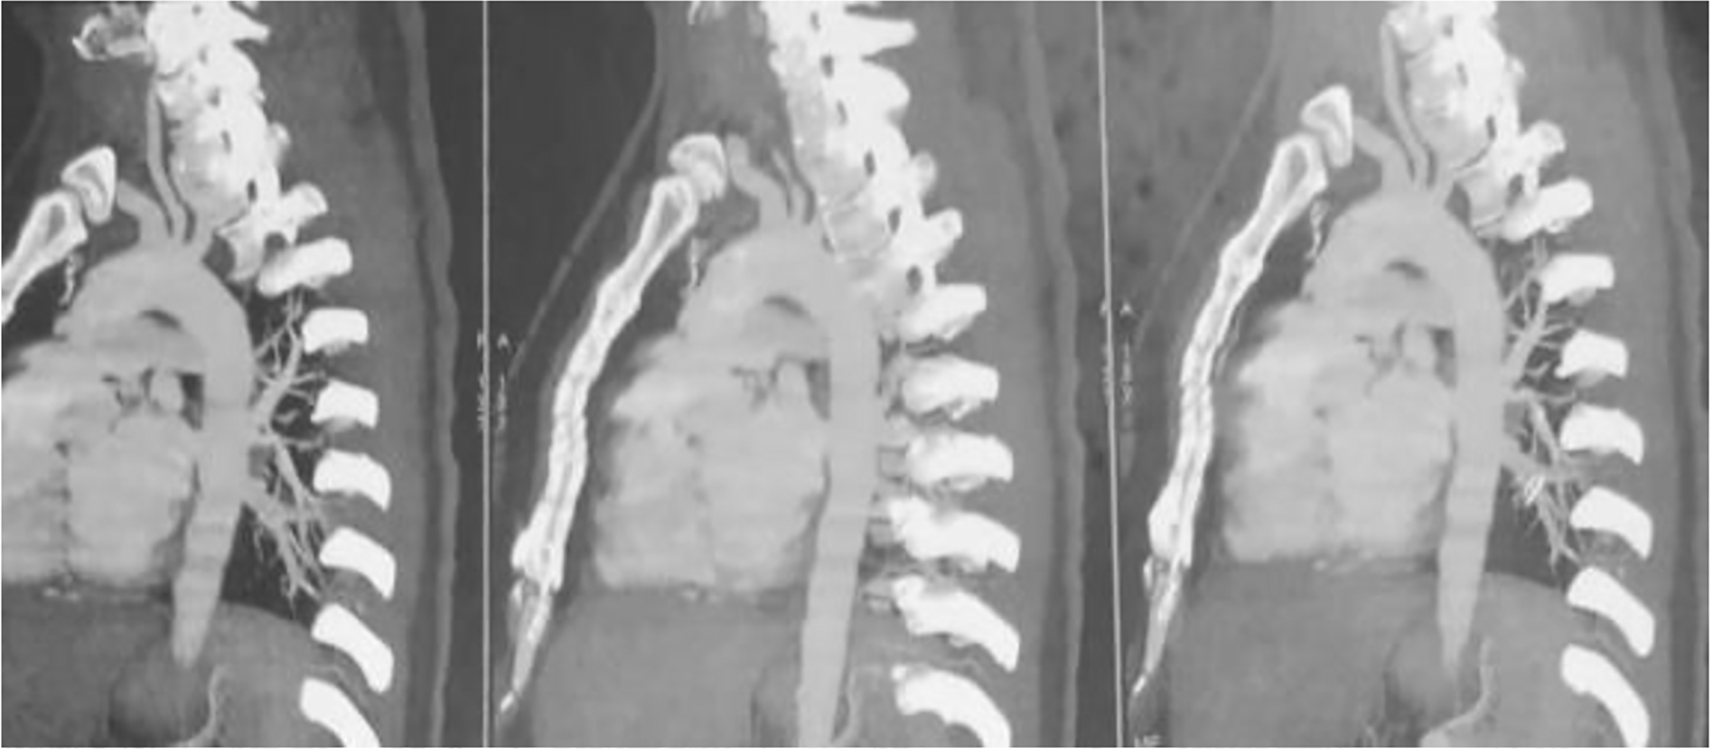

After two hours, the patient developed right hemiplegia and aphasia. A cerebral CT scan revealed a left ischaemic stroke in the anterior junctional territory. CT angiography of the supra-aortic arteries showed a dissection of the left internal carotid artery. However, CT angiography of the aorta revealed no abnormalities (Figure 2). Coronary angiography performed after 48 hours showed dissection of the anterior inter-ventricular artery (Figure 3).